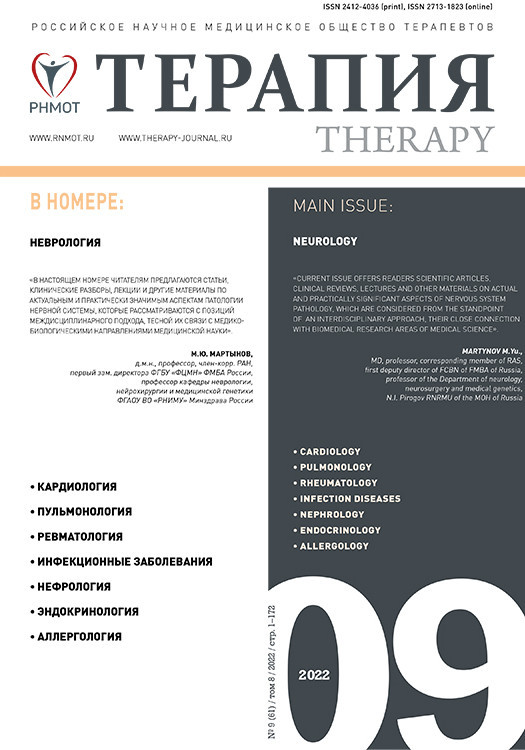

Компьютерная томография (КТ) или магнитно-резонансная томография (МРТ) являются необходимыми методами диагностики СЗОЭ, позволяющими выявить его морфологическую основу – вазогенный отек головного мозга. При классическом варианте СЗОЭ (до 70% всех наблюдений) вазогенный отек мозга локализуется в теменно-затылочных отделах больших полушарий. На КТ он представлен зонами низкой плотности (рис. 1). Методом выбора для окончательной диагностики СЗОЭ служит МРТ. Вазогенный отек головного мозга хорошо визуализируется в режиме МРТ FLAIR (инверсия–восстановление с подавлением сигнала от воды) в виде гиперинтенсивного сигнала (рис. 2) [8, 9].